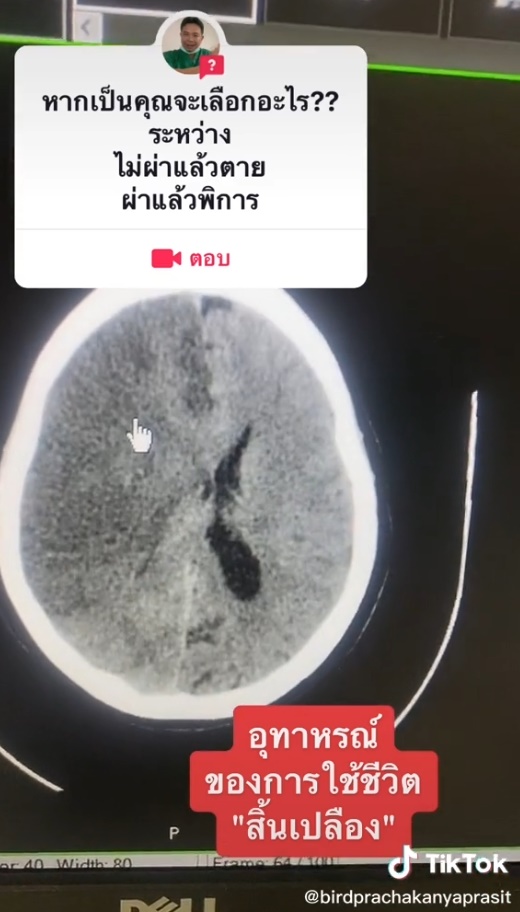

ผลการซีทีสแกน พบว่า สมองซีกขวาบวม มีลิ่มเลือดอุดตันเส้นเลือดทั้งลำ ตอนนี้ผ่านไปวันที่ 2 สมองบวมมากขึ้นกว่าเดิม ช่องน้ำเลี้ยงสมองหายไปหมดแล้ว